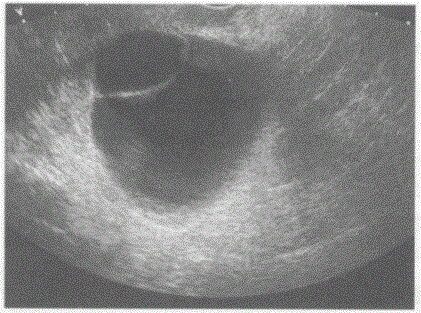

问题 临床资料:女,51岁,常规体检。 超声综合描述:经阴道扫查右卵巢可见4.5cm×4.8cm无回声区,边界清晰,形态尚规则,壁薄光滑,内可见完整分隔。 超声提示:

选项 A.右卵巢囊肿 B.右卵巢畸胎瘤 C.右卵巢巧克力囊肿 D.右卵巢黄素囊肿

答案 A